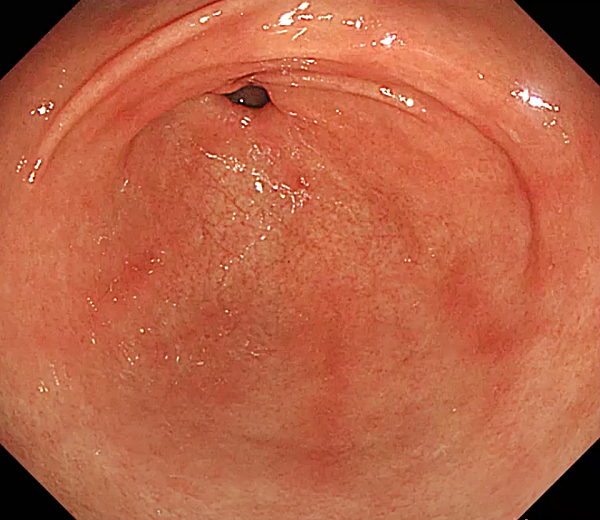

위축성 위염

- 위 점막이 얇아지고 위산 분비 기능이 저하되는 만성 위염입니다.

- 헬리코박터 파일로리균 감염, 자가면역 질환, 유전적 요인 등으로 인해 발생합니다.

- 소화불량, 속쓰림, 복부 팽만감, 식욕 부진 등의 증상이 나타날 수 있지만, 증상이 없는 경우도 많습니다.

- 위축성 위염은 위암 발생 위험을 높일 수 있으므로 정기적인 검진과 관리가 중요합니다.

- 헬리코박터 파일로리 제균 치료, 위산 분비 억제제, 점막 보호제 등을 사용하여 치료합니다.